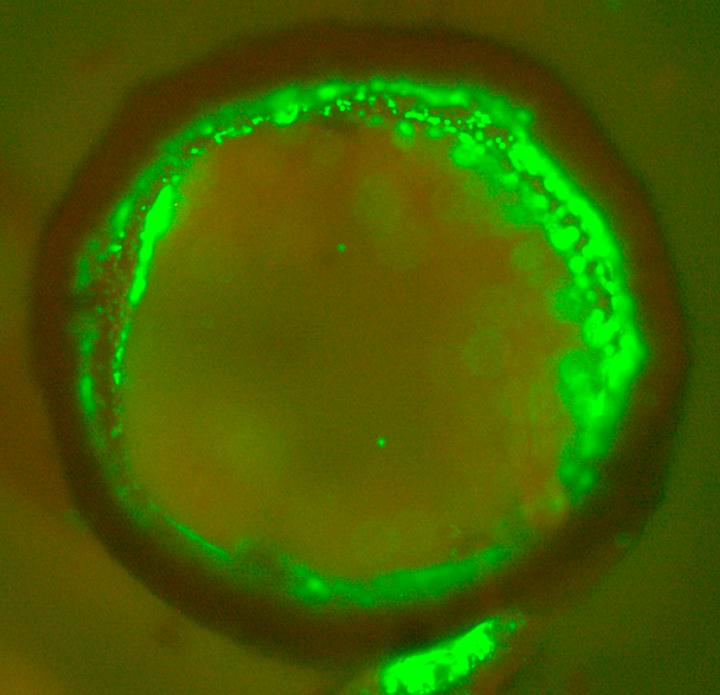

An international team of scientists have discovered a new material that can be 3D printed to create tissue-like vascular structures.

In a new study published today in Nature Communications , led by Professor Alvaro Mata at the University of Nottingham and Queen Mary University London, researchers have developed a way to 3D print graphene oxide with a protein which can organise into tubular structures that replicate some properties of vascular tissue.

The material can then be used as a 3D printing bioink to print structures with intricate geometries and resolutions down to 10 ?m. The research team have demonstrated the capacity to build vascular-like structures in the presence of cells and exhibiting biologically relevant chemical and mechanical properties.